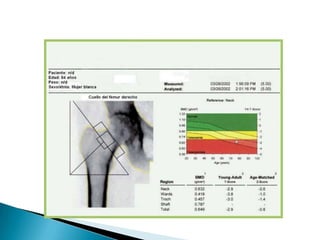

1) Expertos en la prevención, diagnóstico, tratamiento y educación de los pacientes con artritis y enfermedades musculoesqueléticas.2) Manejo de procedimientos invasivos especializados (ej: Biopsias, artroscopías, sinovectomias, etc) en pacientes con enfermedades reumáticas.3) Manejo del dolor crónico en pacientes afectados por enfermedades reumáticas crónicas. 4) Manejo de la Osteoporosis y sus métodos de diagnóstico como losestudios de absorciometria dual de rayos X y métodos periféricos, incluido el ultrasonido cuantitativo.Papel del Reumatologo

1) Expertos enla prevención, diagnóstico, tratamiento y educación de los pacientes con artritis y enfermedades musculoesqueléticas.2) Manejo de procedimientos invasivos especializados (ej: Biopsias, artroscopías, sinovectomias, etc) en pacientes con enfermedades reumáticas.3) Manejo del dolor crónico en pacientes afectados por enfermedades reumáticas crónicas. 4) Manejo de la Osteoporosis y sus métodos de diagnóstico como losestudios de absorciometria dual de rayos X y métodos periféricos, incluido el ultrasonido cuantitativo.Papel del Reumatologo